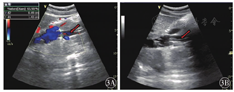

患者2女性,53岁。因"腹部持续性隐痛,阵发性加重,偶有腰背部疼痛,发热2 d"于2018年11月16日入院。入院当天行彩色多普勒超声检查发现下腔静脉近段血流充盈缺损,管腔内可见一规则、边缘整齐、高回声的实质性、漂浮条索状物,狭窄率为60%~70%,长约6.0 cm,上缘距右心房约3.0 cm。右肾静脉内无血流显示(图5)。由于此漂浮物较长,距右心房距离较近,无法行下腔静脉滤器置入术,于2018年11月26日全麻下行右肾切除术+下腔静脉瘤栓切除术,术中剖腹探查发现右肾静脉内无血流充盈,可扪及实性质韧肿物由肾实质内延伸至下腔静脉内,沿右肾静脉根部剖开下腔静脉壁,见静脉内黄色光滑质韧瘤栓,呈漂浮样与静脉无粘连,予以取出(图6)。术后患者生命体征平稳。术后病理诊断:右肾血管平滑肌脂肪瘤。患者术后行彩色多普勒超声检查,提示下腔静脉内管壁光滑,管腔内径正常,血流通畅,充盈良好(图7)。患者于2018年12月5日出院。